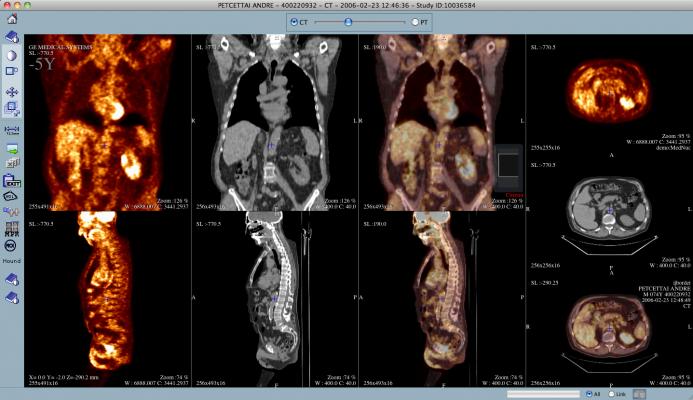

When it comes to determining how the heart is functioning or whether cancer is present, doctors and patients rely on diagnostic tests using a radioactive medical-grade isotope made from Mo-99. Mo-99 is historically produced using HEU, an extremely dangerous substance used in nuclear weapons.